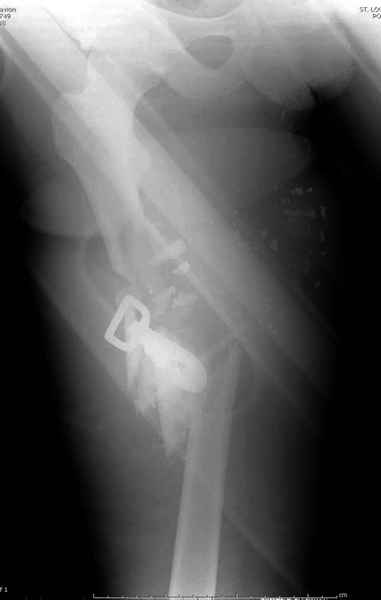

3 такие раны после удаления пули и остатков одежды можно закрыть первично